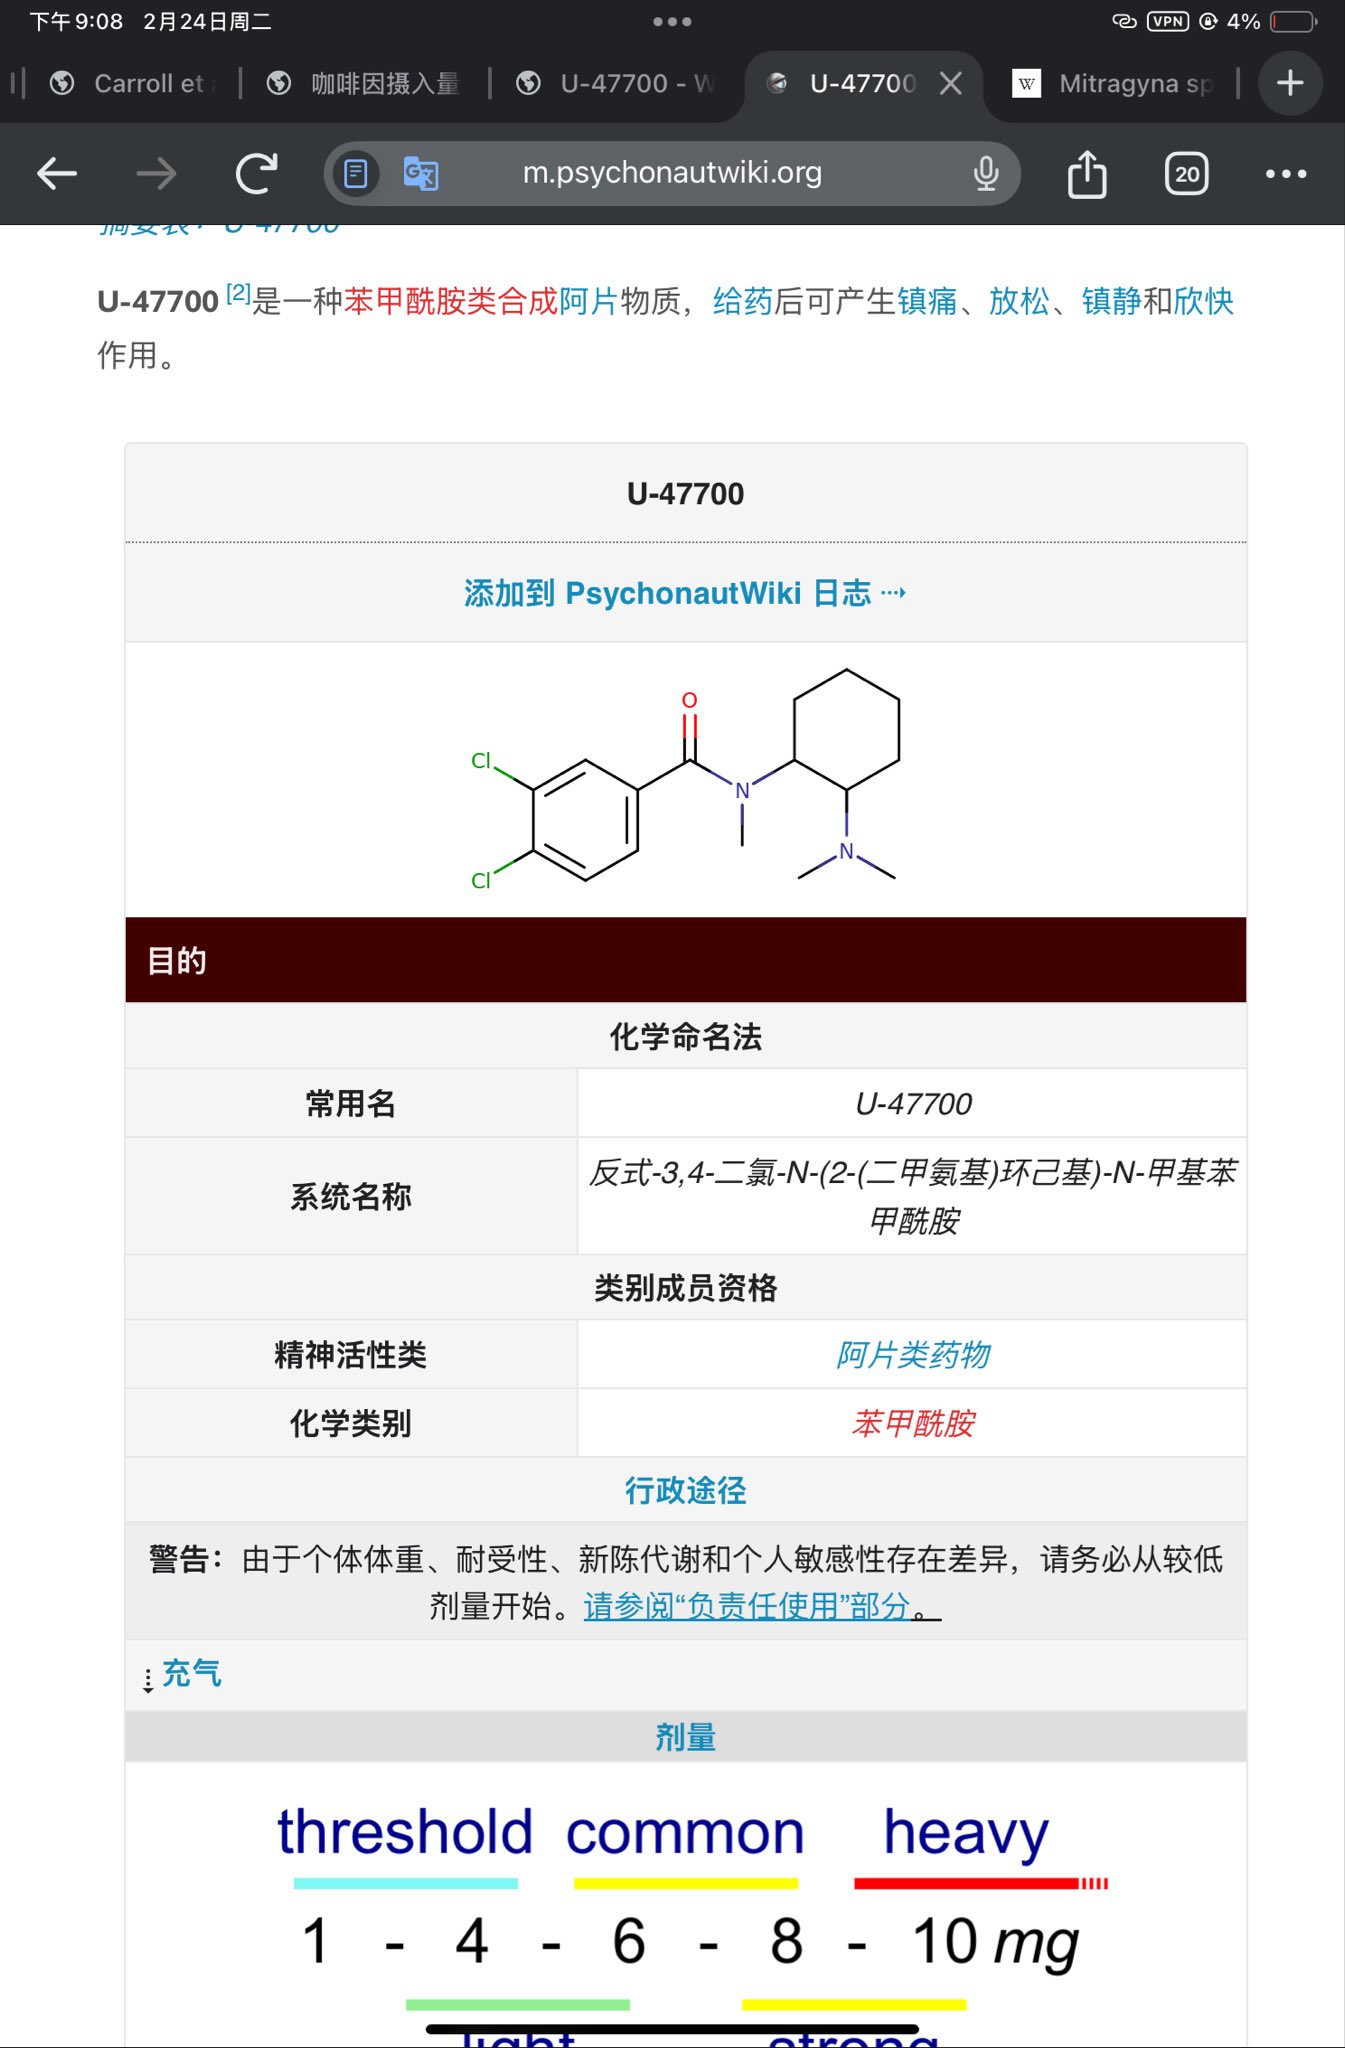

首先,从定义上讲,“反解离(anti-dissociative)”并不是一个标准的医学术语或者广泛认同的药理学分类。在正规资料,比如医学文献、维基百科、精神药理学教科书中,目前并没有“反解离药物”这个正式概念。

看上去像是为了描述某类特定效应而创造的术语(可能是nmda受体活性增强),用来对抗因NMDA受体拮抗剂(比如氯胺酮、DXM、PCP等)引发的解离体验(dissociation)。

那么更常见的是将其归入认知增强剂(cognitive enhancers),特别是改善认知连接性(connectivity)和现实感知(reality testing)的类型。

但其实在药理学上,单纯用“受体激动剂”来逆转“受体拮抗剂”的效应,有时会导致过度激活。

对于NMDA受体而言,过强的NMDA活化本身就与兴奋性毒性(excitotoxicity)和精神病样症状(psychotomimetic effects)有关,比如谷氨酸风暴可以引发严重的焦虑、妄想、乃至癫痫。

也就是说,简单地“激动-解除拮抗”在中枢神经系统是很危险的做法,尤其是对于易感个体(如有精神分裂素质的人)。

科学的处理方式一般是通过更细致的调节,比如微调NMDA/AMPA平衡、调节其他辅助途径(如GABA、5-HT、mGluR受体),而不是简单粗暴地用“NMDA增强剂”去顶回去。

而临床处理药物中毒中,其实医生更常用的做法是保守、支持性的治疗,比如补液,促进代谢,必要时镇静,以及监测生命体征防治并发症。

药物拮抗与受体激动之间,往往牵扯到的是复杂的适应性变化(receptor upregulation/downregulation),

不是简单的“给多一点刺激就能抵消”的关系